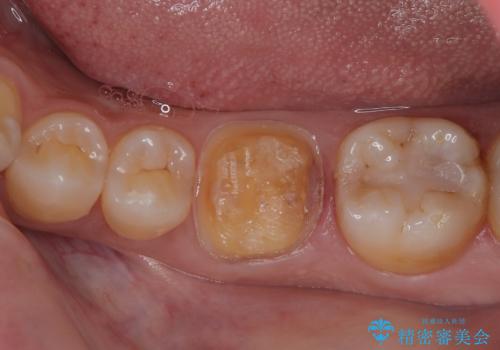

- 左下の詰め物が割れたとのことで来院された患者様です。現在に至るまで二度セラミックの詰め物(セラミックインレー)が割れているので強度面を考慮しセラミックの被せもの(セラミッククラウン)にて治療を行っていくことにしました。

拡大鏡視野下でセラミックインレー、虫歯の除去を行い、オールセラミッククラウンに適した形に整えました。